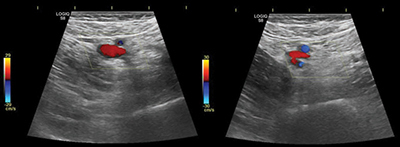

教学要点:虽然深静脉血栓是腰椎关节置换术后常见的并发症,但先天性动静脉瘘等罕见并发症也可能出现类似情况,这就凸显了广泛鉴别诊断和适当影像学检查对及时处理的重要性。

Teaching point: Although deep vein thrombosis is a common concern after lumbar arthrodesis, rare complications such as an iatrogenic arteriovenous fistula can present similarly, highlighting the importance of a broad, differential diagnosis and appropriate imaging for timely management.